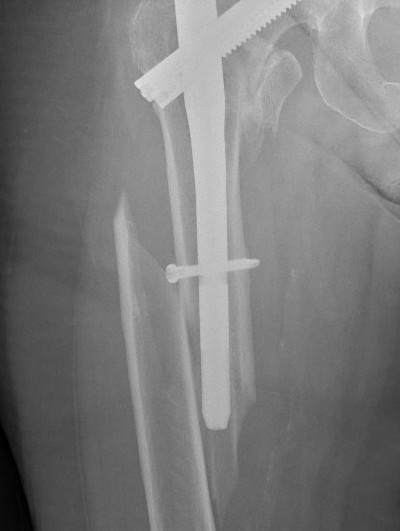

Cephalomedullary nail / Proximal femoral nail

Mechanical advantages

- load sharing rather than load bearing

- decreases lever arm

- supports medial cortex

Surgical advantages

- smaller incision / minimally invasive

- reduced blood loss

- shorter surgical times

Indications

- reverse oblique

- unstable fracture / loss of lateral buttress / loss posteromedial support

- subtrochanteric extension